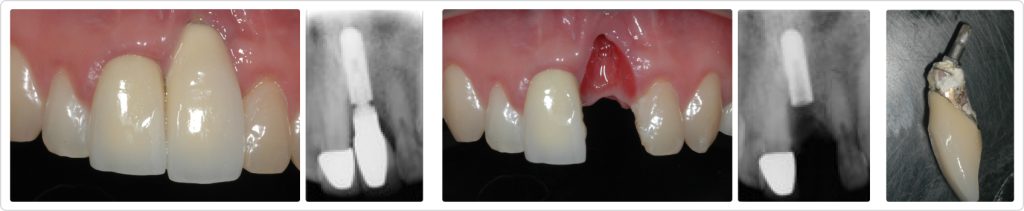

This patient had been in an auto accident that avulsed Tooth #9. His dentist at the time replaced the avulsed tooth with an immediate implant-supported restoration, but the patient was unhappy with the outcome and presented to our practice one year after the restoration had been delivered, seeking other solutions.

Several elements of his previous treatment (Figs. 1–5) were visibly deficient:

- The restoration was ill-fitting, and tartar and plaque had accumulated at the implant interface.

- The implant was placed too far apical and facial, creating an asymmetric gingival level when viewed alongside the adjacent central incisor. (When working with central incisors, care must be taken to provide gingival symmetry to attain an esthetic outcome, and this was far from it.)